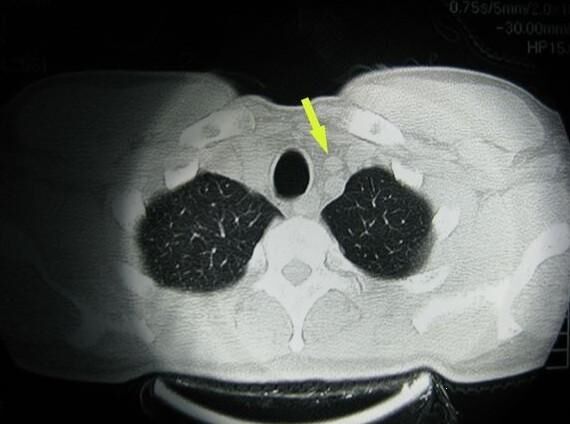

美國(guó)看?。好绹?guó)如何治療胸腺瘤?